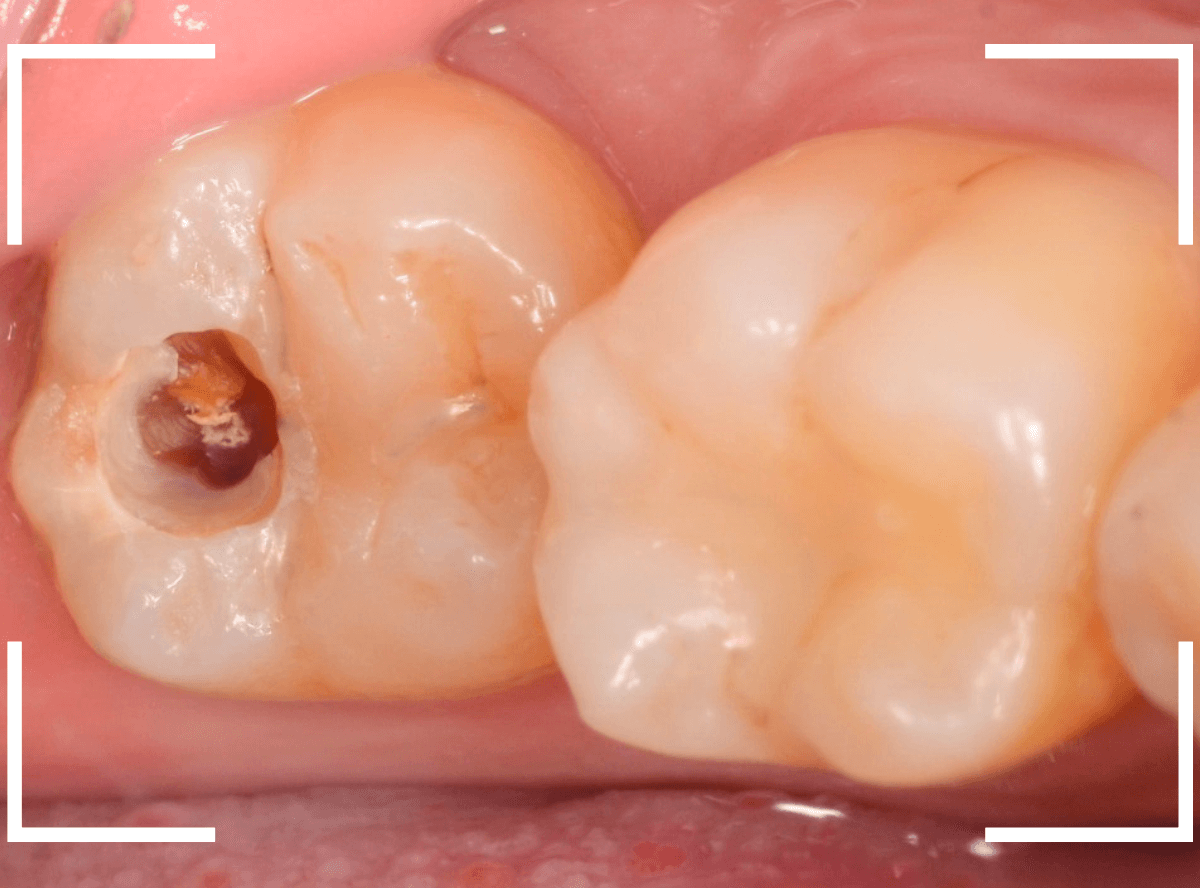

Case.12 仮つめ中のレジンの下がひどい虫歯

今回は、他院で治療途中で離脱後、放置してしまった患者さんの例です。

一目瞭然かと思いますが、仮つめ?にしていたレジンがかけて、中が虫歯になっています。

レントゲン写真で確認します。

青い部分が歯の神経で、赤い部分が虫歯です。

神経寸前まで虫歯が進行しているのがわかります。

ここまで虫歯が進行していたら、何か症状が出てもおかしくないのですが、特に症状はないそうです。

おかげで、本人はYAVAY状況に気づいていません

(><)

本人にYAVAY状況を説明して、早急に治療を開始します。

レジンを除去すると、すぐに大きな虫歯が見えてきました。

赤い部分が虫歯です。

今にも神経が見えてしまいそうで怖いです。

エキスカを使って、少しずつ虫歯を除去します。

ほぼ、全ての虫歯を除去したところです。

〇部が神経の入り口です。

ここをお薬で保護し、セメントで蓋をしてしばらく様子をみます。

痛みが出て取れなけば・・・改めて神経を取る治療が必要になります(>_<)